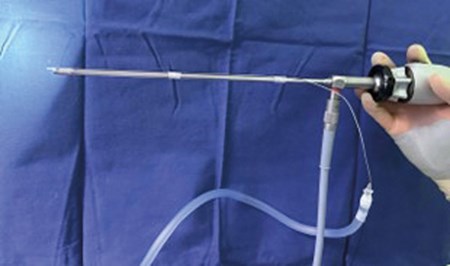

Figure 3: The correct position of the fibre with respect to the endoscope.

- The best position of the fibre is achieved by looking at the video monitor. Once the tip of the fibre is exactly in the centre of the screen (Figure 2), it is fixed with Steri-StripTM. The first band of Steri-Strip™ is placed a couple of millimetres away from the superior edge of the endoscope, firmly holding the fibre and surrounding the entire circumference of it, and reinforcing with a second band over the first one. Then two more bands are used to hold the fibre in the same manner in the middle and posterior ends of the endoscope (Figure 3). Recently, a disposable custom-made steel tube to pass the fibre through has been tried, fixed just the same way on top of the endoscope. The advantage of the latter is that it is easy to interchange 300 µm and 400 µm fibres as needed (Figure 4).

Figure 4: The Steri-StripTM bands holding the fibre on top of the endoscope.